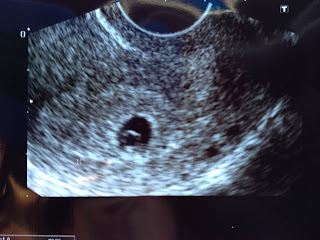

The following week I went in for my annual exam and to discuss prenatal appointments. Today we had our first real prenatal appointment. I had no idea when my last period was, so I was clueless about how far along we might be. We estimated about 6 weeks and scheduled an ultrasound for today. We were off on the date it seems. We are only about 5 weeks pregnant right now, but we have a priceless picture and we heard the most beautiful sound I have ever heard. This tiny little flicker on the screen gave off a strong, loud heartbeat!